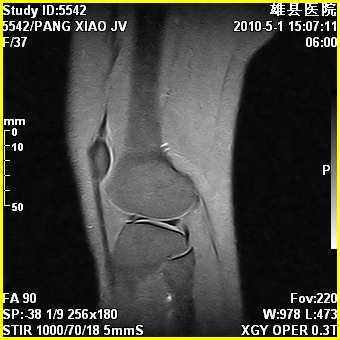

标题: MRI2894:患者右膝关节疼痛两月余,无明显外伤史 [打印本页]

标题: MRI2894:患者右膝关节疼痛两月余,无明显外伤史

右股骨下端前内侧类圆形异常信号,位于干骺端,呈长t1长t2改变,但信号不均,t1图上病灶中心见小片状稍高信号影,t2图上见散在稍低信号影,stir像呈高信号,因病灶较小,缺乏特征性改变,结合患者年龄及部位,考虑嗜酸性肉芽肿可能性大。胫骨关节面下的小囊状异常信号,如果一元论考虑则为嗜酸性肉芽肿,不过发生在这个部位的少见,二元论考虑为邻关节骨囊肿。半月板与前后交叉韧带均未见异常。

右股骨下端前内侧干骺端囊性良性病变,考虑 1内生软骨瘤 2骨囊肿 3肉芽肿。